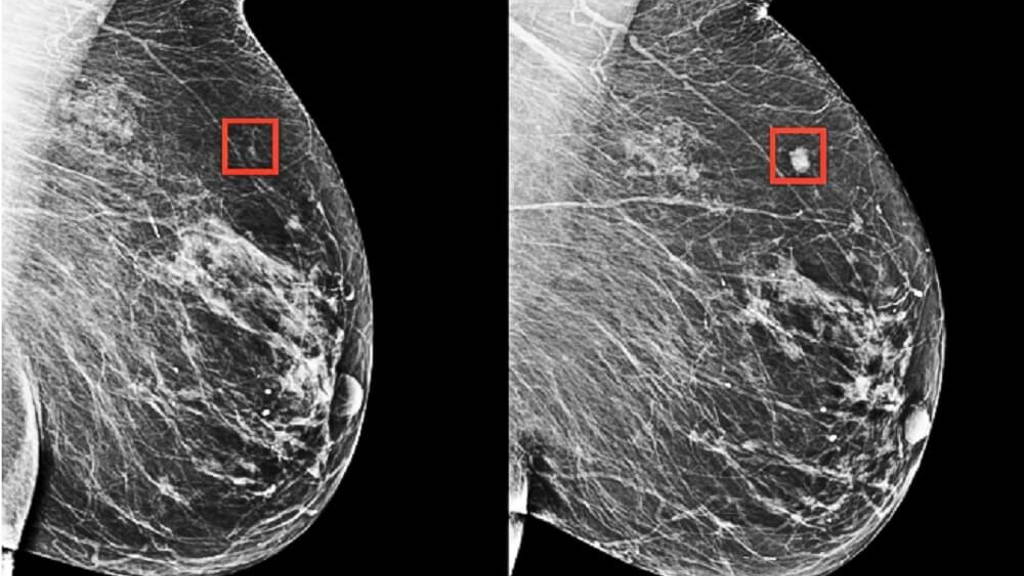

The model detected patterns too subtle for the human eye to detect

Rather than manually identifying the patterns in a mammogram that drive future cancer, the MIT/MGH team trained a deep-learning model to deduce the patterns directly from the data. Using information from more than 90,000 mammograms, the model detected patterns too subtle for the human eye to detect.

The team's model was shown to be able to identify a woman at high risk of breast cancer four years (left) before it developed (right) (image courtesy of the researchers).